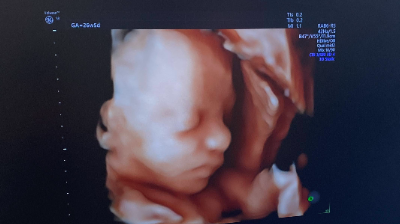

La Clínica Salus Infirmorum continua apostant per la innovació en el diagnòstic per la imatge amb l'objectiu d'oferir una atenció cada vegada més integral i personalitzada. En aquest sentit, la consulta de ginecologia i obstetrícia del doctor Eduardo Reyes i de la doctora Anna Maroto ha incorporat, des de fa ben poques setmanes, un ecògraf d’última generació que ofereix imatges d'alta definició (claredat i realisme) del moviment en temps real del fetus. D'aquesta manera, el metge especialista pot fer un seguiment més precís del desenvolupament de l’embaràs i, alhora, una valoració detallada de la salut ginecològica de les dones.

Les pacients que vagin a la consulta d'obstetrícia s'enduran un regal per a tota la vida, ja que se'ls farà entrega d'una carpeta amb fotos i un USB amb vídeos del futur nadó per immortalitzar aquests moments tan importants en la vida de les parelles.